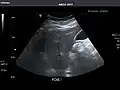

Liver

Ultrasonography of the liver with some standard measurements[6]

In patients with deranged liver function tests, ultrasound may show increased liver size (hepatomegaly), increased reflectiveness (which might, for example, indicate cholestasis), gallbladder or bile duct diseases, or a tumor in the liver.

Ultrasonography of liver tumors involves two stages: detection and characterization. Tumor detection is based on the performance of the method and should include morphometric information (three axes dimensions, volume) and topographic information (number, location specifying liver segment and lobe/lobes). The specification of these data is important for staging liver tumors and prognosis. Tumor characterization is a complex process based on a sum of criteria leading towards tumor nature definition. Often, other diagnostic procedures, especially interventional ones, are no longer necessary. Tumor characterization using the ultrasound method will be based on the following elements: consistency (solid, liquid, mixed), echogenicity, structure appearance (homogeneous or heterogeneous), delineation from adjacent liver parenchyma (capsular, imprecise), elasticity, posterior acoustic enhancement effect, the relation with neighboring organs or structures (displacement, invasion), vasculature (presence and characteristics on Doppler ultrasonography and contrast-enhanced ultrasound (CEUS).